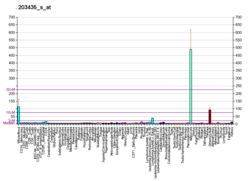

Neprilysin (/ˌnɛprɪˈlaɪsɪn/; also known as membrane metallo-endopeptidase (MME), neutral endopeptidase (NEP), cluster of differentiation 10 (CD10) and common acute lymphoblastic leukemia antigen (CALLA)) is an enzyme that in humans is encoded by the MME gene. Neprilysin is a zinc-dependent metalloprotease that cleaves peptides at the amino side of hydrophobic residues and inactivates several peptide hormones including glucagon, enkephalins, substance P, neurotensin, oxytocin, and bradykinin.[5] It also degrades the amyloid beta peptide whose abnormal folding and aggregation in neural tissue has been implicated as a cause of Alzheimer's disease. Synthesized as a membrane-bound protein, the neprilysin ectodomain is released into the extracellular domain after it has been transported from the Golgi apparatus to the cell surface.

Neprilysin is expressed in a wide variety of tissues and is particularly abundant in kidney. It is also a common acute lymphocytic leukemia antigen that is an important cell surface marker in the diagnosis of human acute lymphocytic leukemia (ALL). This protein is present on leukemic cells of pre-B phenotype, which represent 85% of cases of ALL.[5]

Neprilysin is also associated with other biochemical processes, and is particularly highly expressed in kidney and lung tissues. Inhibitors have been designed with the aim of developing analgesic and antihypertensive agents that act by preventing neprilysin's activity against signaling peptides such as enkephalins, substance P, endothelin, and atrial natriuretic peptide.[13][14]

Associations have been observed between neprilysin expression and various types of cancer; however, the relationship between neprilysin expression and carcinogenesis remains obscure. In cancer biomarker studies, the neprilysin gene is often referred to as CD10 or CALLA. In some types of cancer, such as metastatic carcinoma and some advanced melanomas, neprilysin is overexpressed;[15] in other types, most notably lung cancers, neprilysin is downregulated, and thus unable to modulate the pro-growth autocrine signaling of cancer cells via secreted peptides such as mammalian homologs related to bombesin.[16] Some plant extracts (methanol extracts of Ceropegia rupicola, Kniphofia sumarae, Plectranthus cf barbatus, and an aqueous extract of Pavetta longiflora) were found able to inhibit the enzymatic activity of neutral endopeptidase.[17]